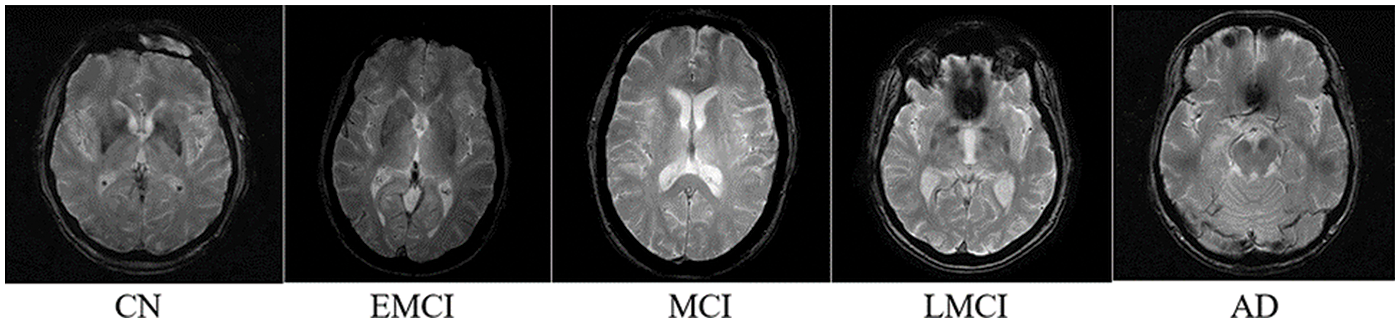

The dataset used in this study is derived from T1-weighted MRI images from ADNI 1 [35]. ADNI 1 is a subset of the MRI neuroimaging of the ADNI database. The original 3D images were converted to 2D images, preprocessed, and formatted into JPG images. The images are of the brain of different patients in different stages of AD. The dataset consists of five classes: Cognitive Normal (CN), Early Mild Cognitive Impairment (EMCI), Mild Cognitive Impairment (MCI), Late Mild Cognitive Impairment (LMCI), and AD (Alzheimer’s Disease). Each image is 256 × 256 pixels. In total, there are 1296 images with 171 AD images, 580 CN images, 240 EMCI images, 72 LMCI images, and 233 MCI images. The sample image of each class is mentioned in Fig. 2. Each class represents a stage of AD.

Figure 2: Sample image of each class of the dataset